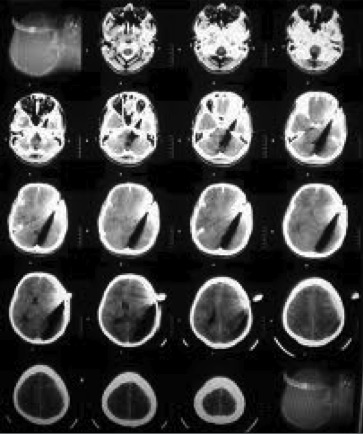

Computed tomography (CT) uses a narrowly collimated beam of x-rays that rotates in a full arc around the patient to produce an image of detailed cross-secional slices. A major advantage of CT is its ability to image bone, soft tissue and blood vessels all at the same time. An array of detectors, positioned at several angles, records those x-rays that pass through the body. The image is created by a computer that calculates tissue absorption and can produce three dimensional reconstructed images representing tissues that demonstrates the densities of the various structures. CT is less sensitive to patient movement than MRI. CT can be performed if you have an implant medical device of any kind, unlike MRI.

Tumor masses, infarctions, bone displacement, and accumulations of fluid may be detected. It is useful for the diagnosis of bony abnormalities including fractures, dislocations, arthritides, ankylosis, and neoplasia. Three dimensional reconstructed images can be produced.